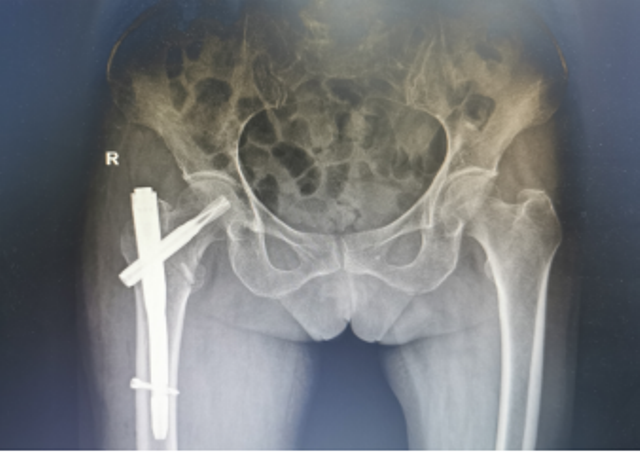

近日,陕西省第四人民医院骨科再次成功为一例91岁高龄的右股骨粗隆间骨折合并冠心病脑梗塞、贫血者实施右股骨粗隆间骨折闭合复位股骨近端抗旋转髓内钉内固定术(简称:PFNA内固定术)。经过术后精心的治疗与护理,患者现已转到康复医学科继续康复治疗。

3月19日,91岁高龄的万奶奶在家行走的时候不慎摔倒在地,当即感到右髋部剧烈疼痛,且不能行走。家属赶紧拨打医院120急诊电话,随后收治骨一科治疗,经检查确诊:右股骨粗隆间粉碎性骨折。

为了手术能顺利开展,骨一科何大鹏主任通过医务科邀请心血管内科、麻醉科、呼吸与危重症医学科、重症医学科等启动围手术期管理专家团队进行会诊,拟定“右股骨粗隆间骨折闭合复位PFNA内固定术”的手术方案,并制定了一套缜密的术前、术中、术后诊疗康复方案,完善术前准备。3月26日,在麻醉科、手术室团队的密切配合下,何大鹏主任、刘玉春、赵鑫医师为万奶奶成功实施手术,整个术程一气呵成,既缩短手术时间,也减少术中出血,有效降低手术给患者带来的伤害。